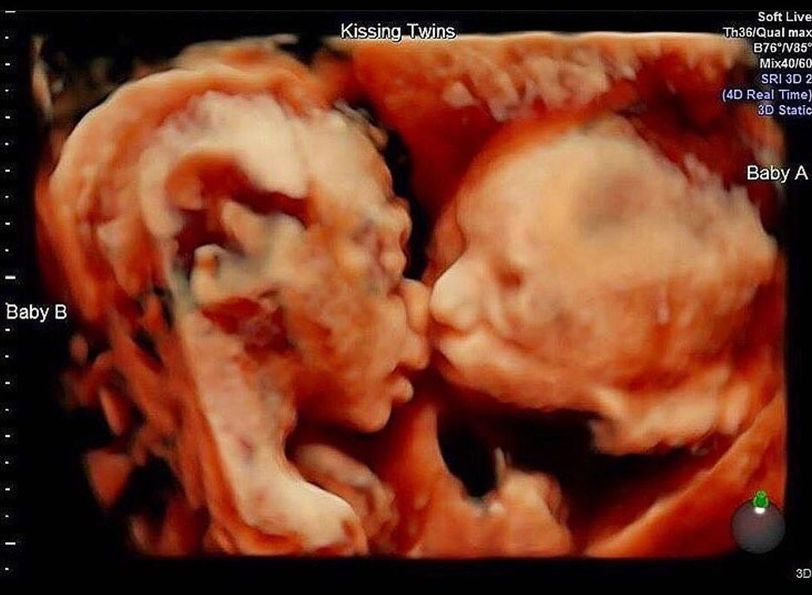

This normal 3D ultrasound scan captured the remarkable moment of twin girls sharing a kiss inside the womb at 25 weeks gestation. Definitely not something we get to see every day! #twins #ultrasound #medicine #medicogram